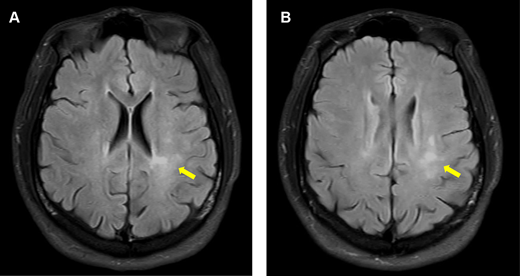

The patient’s magnetic resonance imaging (MRI) at 10 months after the seizure onset. He had intermittent paresthesia in the left leg, and his reflexes were increased in his right arm and leg. A, Axial fluid-attenuated inversion recovery (FLAIR) imaging of the brain shows ill-defined hyperintense lesions in the periventricular regions. B, Sagittal T1-weighted image of the spinal cord shows new short hyperintense lesions affecting the brainstem, the cervical spinal cord, and upper thoracic spinal cord (arrows).